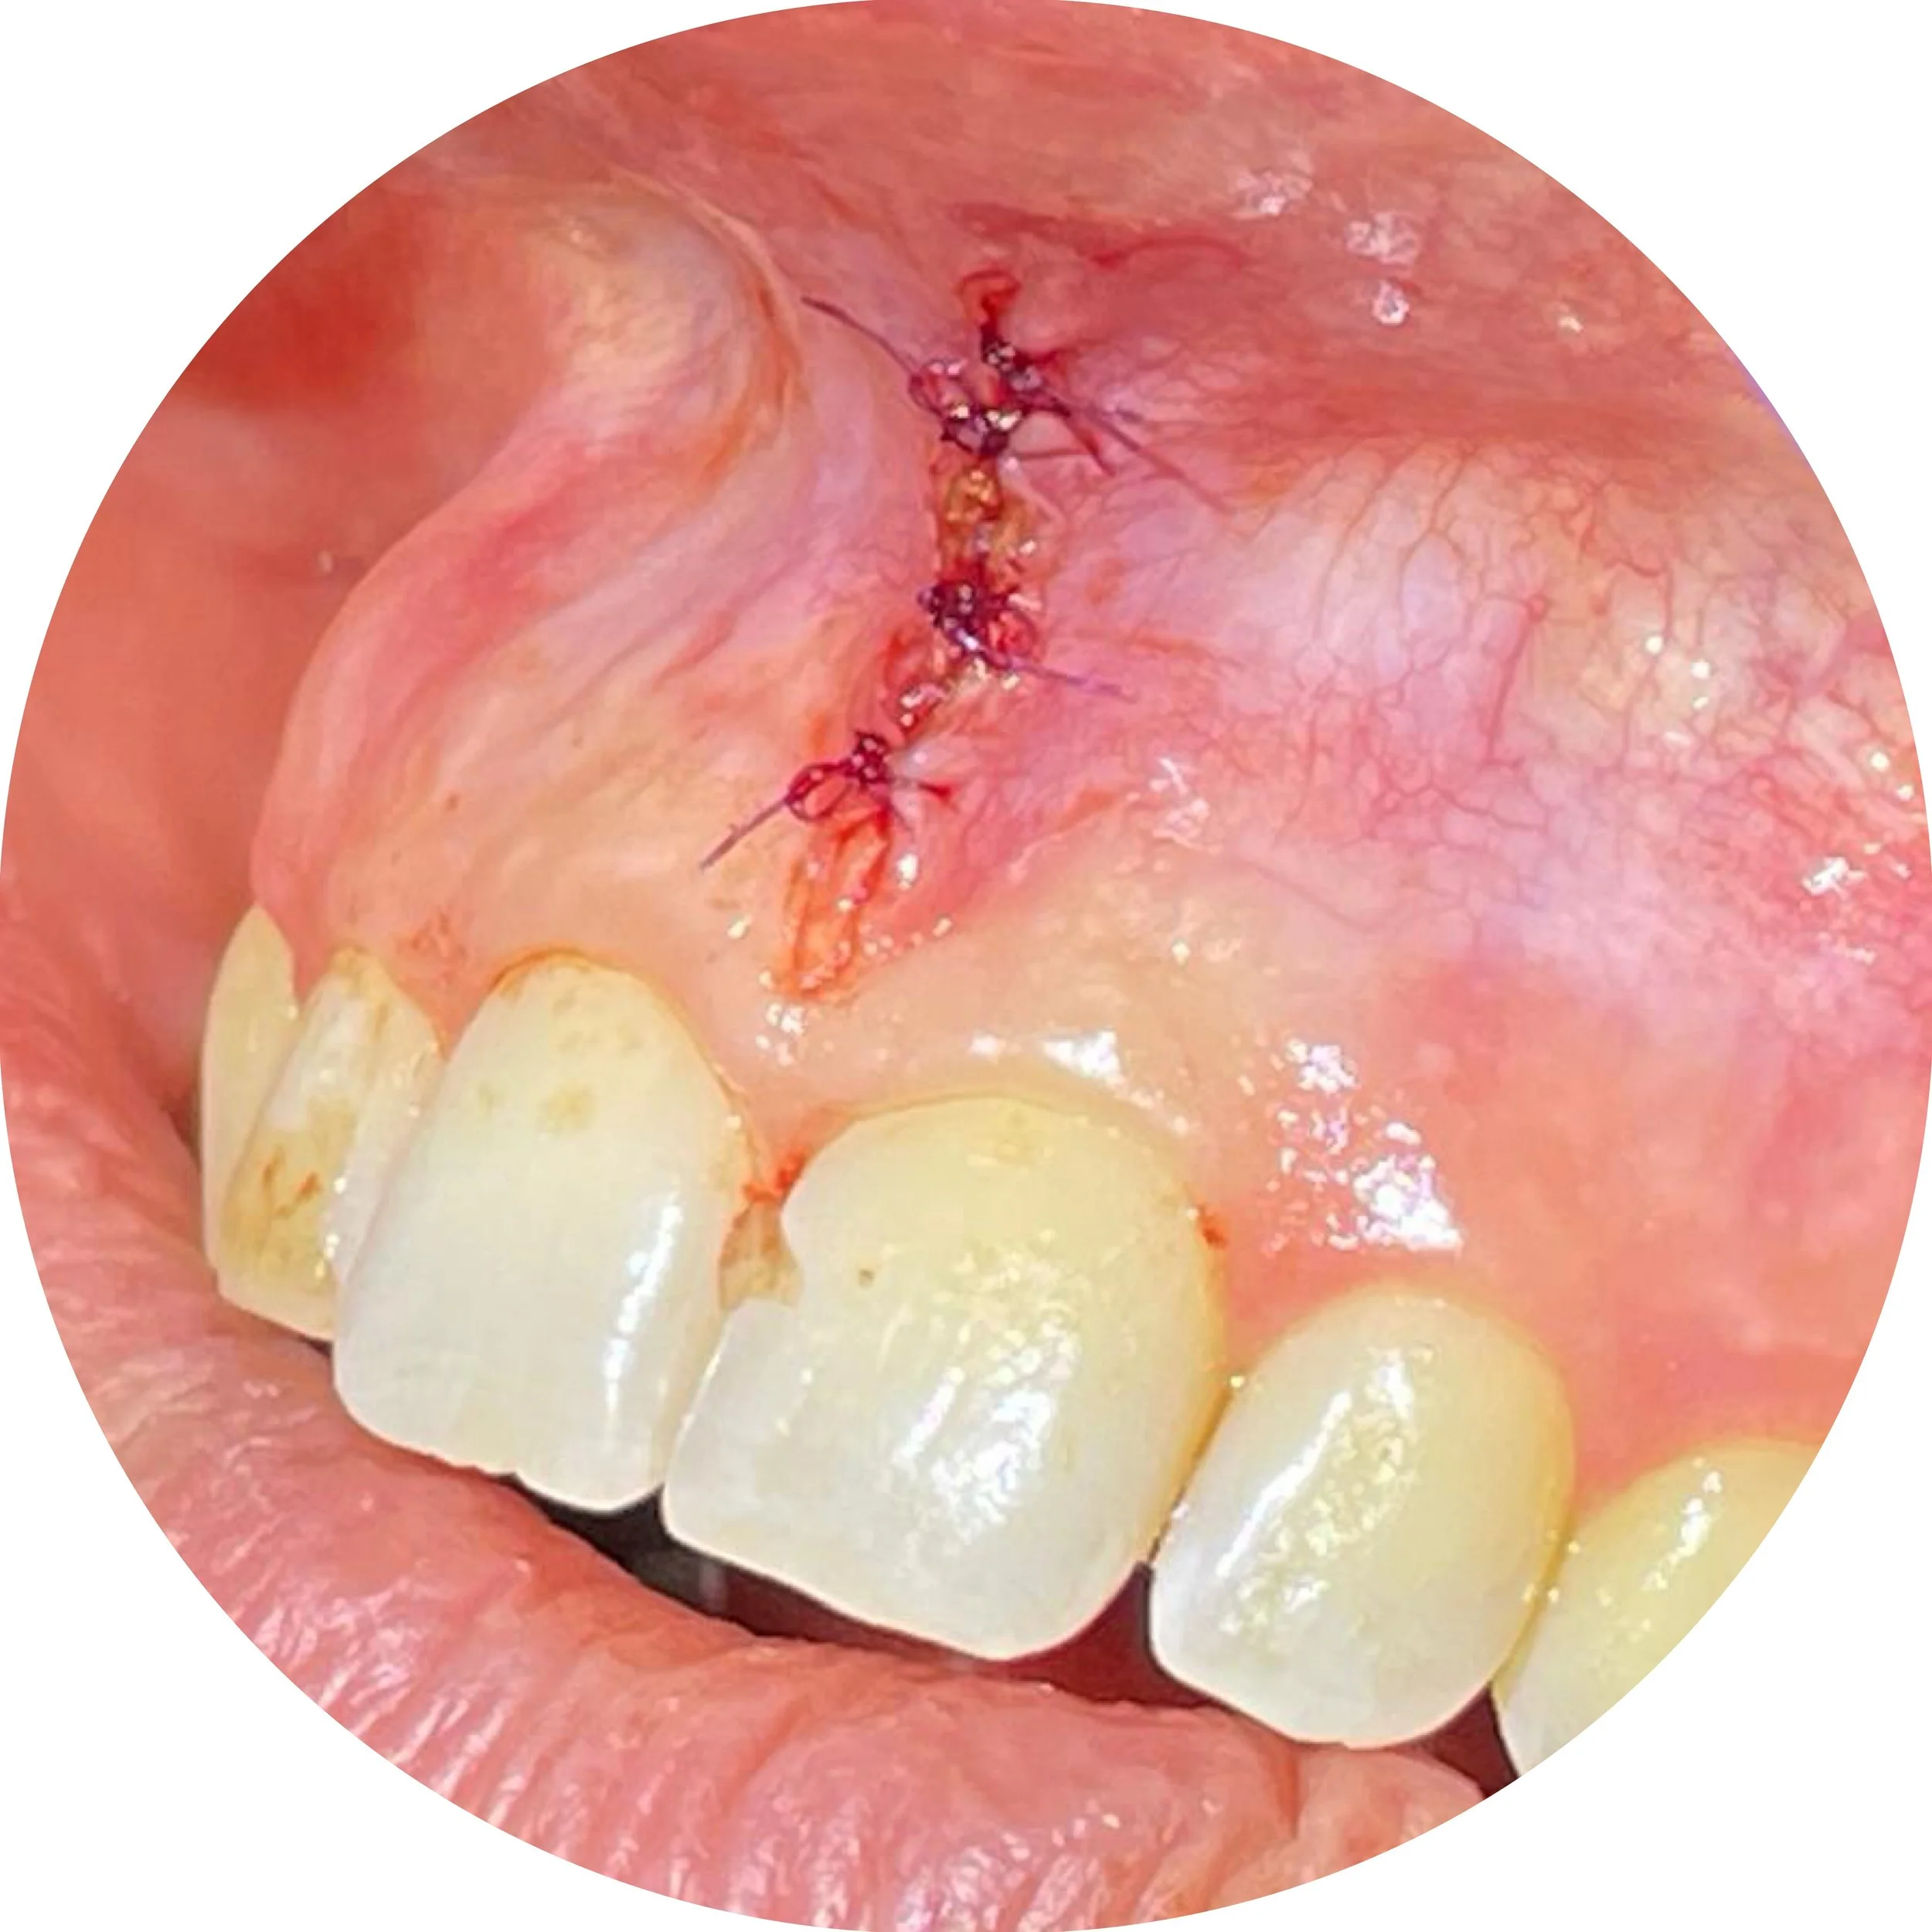

This patient came to our office and mentioned that her upper lip was too high

She was concerned that this was effecting her appearance and speech. It was also making her a mouth breather. These issues were related to the fact that she could not close her lips. We cut the labial (lip) frenulum with a our LightScalpel CO2 laser with minimal bleeding and sutured. The patient noticed she could close her lips much easier.

Close-up of a person's upper front teeth and upper palate with recent dental sutures and healing tissue.